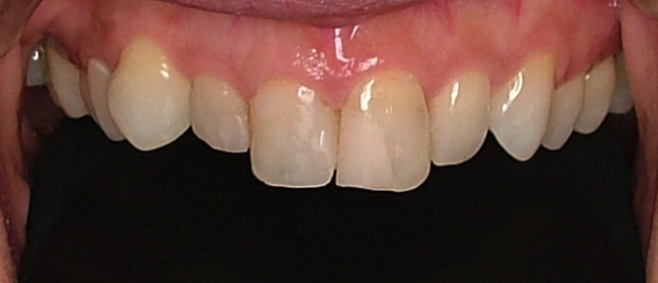

| 治療内容 | ジルコニアセラミック |

|---|---|

| 治療回数 | 3回 |

| 治療時の費用 | 330,000円(税込) ※本症例当時の価格です。最新の費用はこちら |

| リスク・副作用 | 乱暴なブラッシングをすると歯肉が退縮する可能性があります。 |